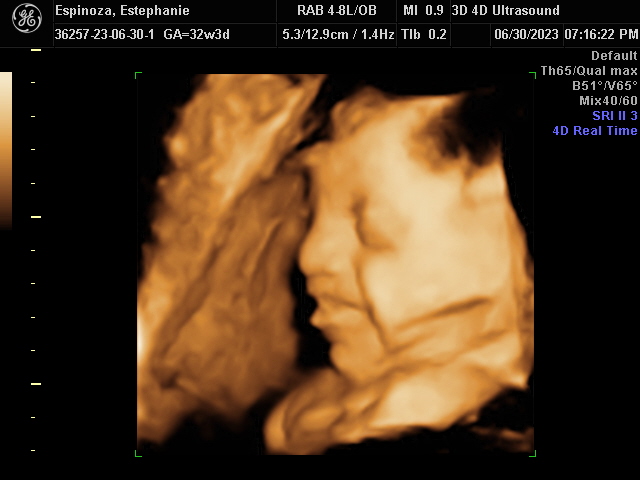

Our Gallery

Explore beautiful moments captured during our 3D and 4D sessions.